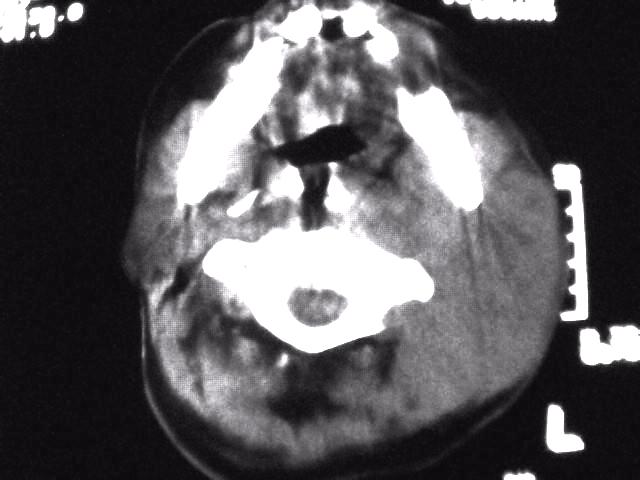

颈部层厚10mm间距10mm连续扫描及增强扫描共24层示:左侧下颈部胸锁乳突肌内侧区域内可见多发软组织结节,密度不均,内可见斑片状低密度区,大小不等,部分融合成块,左侧融合成一块者大约9.0x5.4,与周围肌肉、血管等结构界面不清,骨质未见明显浸润影。左侧锁骨下可见多个软组织结节,与周围界限尚清,左侧锁骨上窝内可见一大软组织肿物,大小约4.7x3.7cm,内密度欠均匀中心可见低密度区。

考虑:左侧颈部及双侧锁骨下多发淋巴结肿。非何杰金氏淋巴瘤可能性大,建议进一步检查。